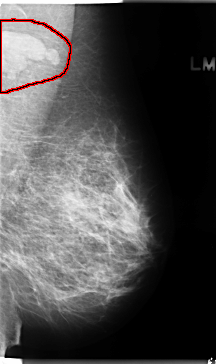

FILE: C_0136_1.LEFT_MLO.OVERLAY

TOTAL_ABNORMALITIES 1

ABNORMALITY 1

LESION_TYPE MASS SHAPE LOBULATED MARGINS CIRCUMSCRIBED

ASSESSMENT 5

SUBTLETY 5

PATHOLOGY MALIGNANT

TOTAL_OUTLINES 1

BOUNDARY